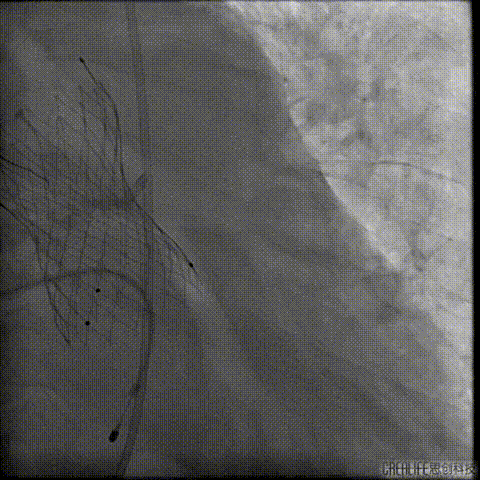

复查冠脉造影

多体位复查冠脉造影

术后即刻